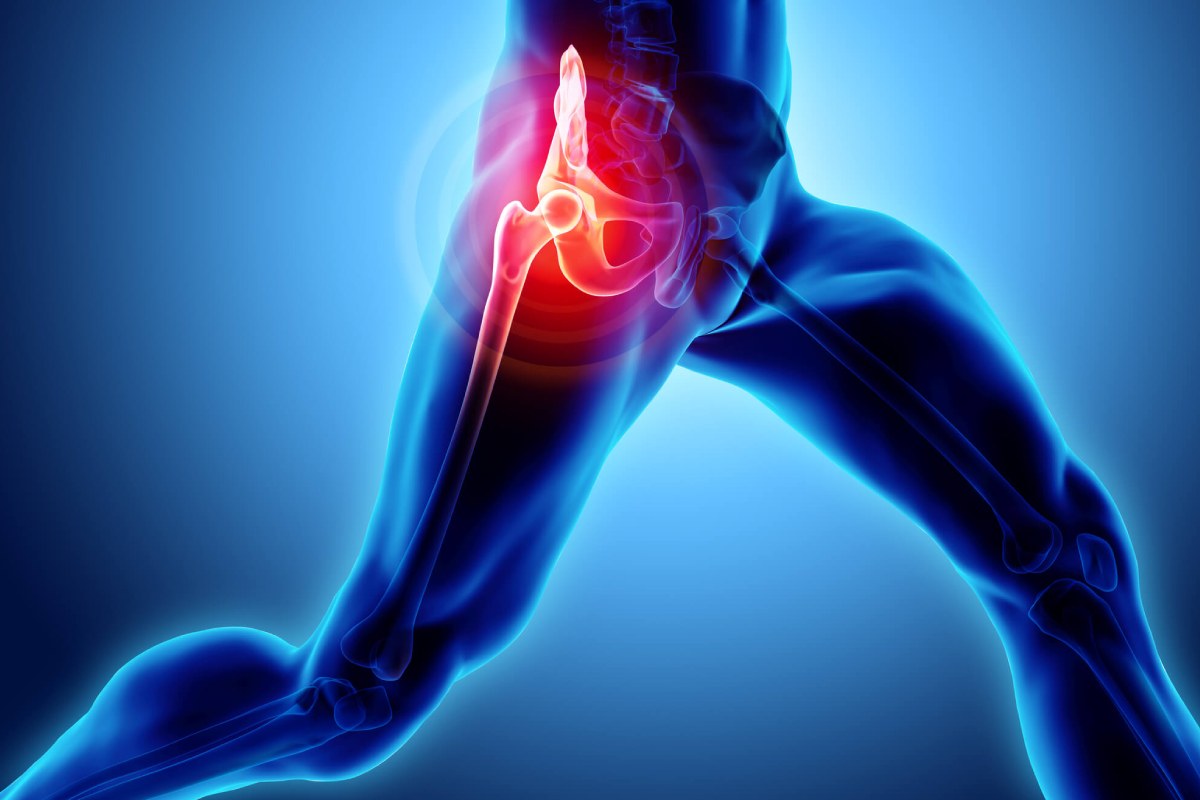

درگیری و آسیب مفصل لگن

علت صدا دادن مفصل ران و لگن